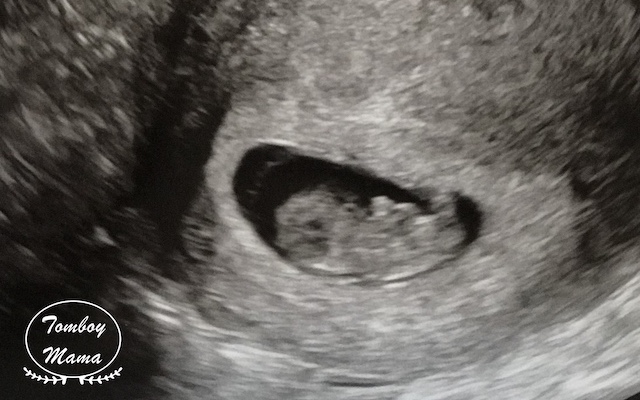

초음파실로 들어가니, Judy Wei 선생님이 아니라 초음파를 보는 분이 따로 계셨다. 마지막 생리 시작일을 물으시고, 임신 9주차이다보니 배 위로 초음파 진료를 시작했... 으나, 잘 보이지 않는다며 질 초음파로 바꾸셨다. 한국에서 방문했던 산부인과처럼 다리가 높게 걸치는 의자가 아니라, 아래로 내리고 잘 덮어주신데다가 매우 숙련된 솜씨라(?) 별로 불편함은 못 느꼈다. 모든 준비를 마치고, 남편이 들어왔다.

그렇게 튼튼이 모습을 별 설명 없이 보여주셨는데, 움직이길래 '움직인거에요?' 했다. 그러고나서는 감격에 벅차 눈물이 차올랐.. 다기 보다는, '오, 잘 살아있구나' 하는 생각이 들었다. 남편도 보아하니 감격보다는 신기함이 더 큰 것 같았다. 나중에 지나고나서 물어보니, SF 영화에서 보는 외계인 검사 장면ㅋㅋㅋㅋ-_- 같았다고 한다. 아기는 주수에 맞게 잘 크고 있다고 했다. 그리고나서 보여주신 아기 심장 뛰는 모습! 이때 '열심히 자라주고 있구나!' 하는 생각과 함께 책임감이 들면서 조금 뭉클했다. 우리는 이렇게 심장 소리는 듣지 못하고, 보기만 했다. :)

한국에서는 다들 5-6주차에 첫 초음파 진료받으면서 아기집을 보던데, 나는 9주차 넘어 이미 움직이고 있는 녀석을 보니 복합한 감정들이 하나하나 익숙해질 새 없이 올라왔다. 그래서인지 기다리고 기다리던 순간인데, 뭔가 너무 훅- 들어온 느낌. 아무래도 임신에 대한 확신이 100%는 아닌 때라, 그 순간에는 안도감 가장 컸던 것 같다.